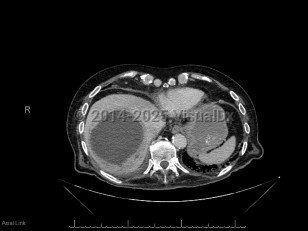

Pyogenic liver abscess

A pyogenic liver abscess is a collection of pus in the liver as the result of bacterial (or rarely fungal) infection.

The two most common routes that pathogens use to invade the liver and cause an abscess are through the biliary tree (if the biliary tree is obstructed, then cholangitis may follow, which can be complicated by hepatic abscess formation) and through the portal venous system (the portal venous system provides drainage of intraabdominal organs, and pathogens causing diverticulitis or appendicitis, for example, will drain through the portal venous system and may form hepatic abscesses). Liver abscesses may also form due to hematogenous seeding of the liver in the setting of bacteremia. Other intraabdominal abscesses may enlarge and involve the liver by contiguous spread. Rarely, pathogens may seed the liver in the setting of anatomic abnormalities (eg, in the setting of a liver hematoma) or due to direct inoculation in the setting of trauma. In 20%-40% of cases, no obvious cause for the liver abscess is identified.

Many organisms can cause a pyogenic liver abscess, and many abscesses are polymicrobial. Common pathogens include Escherichia coli and Klebsiella species (including the hypermucoid strains of Klebsiella pneumoniae that are a major cause of liver abscess in Asia). Anaerobic organisms are frequently involved, and gram-positive organisms including Streptococcus species and Staphylococcus aureus can also cause abscesses. Candida species may also be involved. Clostridium perfringens liver abscesses can cause hemolysis.

The symptoms of pyogenic liver abscess are nonspecific. The two most common symptoms are fever and abdominal pain. In one review, patients had symptoms for a median of 14 days (range 1-90 days) prior to hospital admission. Some patients will have associated nausea, night sweats, and weight loss. A minority of patients have jaundice. Laboratory evaluation will usually reveal abnormal liver enzymes and an elevated white blood cell count.